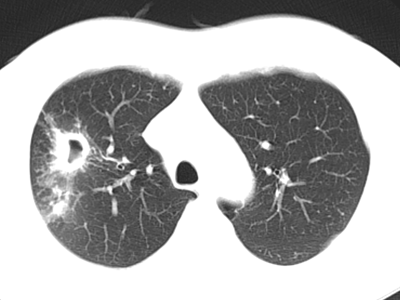

3. 继发性肺结核:继发性肺结核胸部影像表现多样。轻者主要表现为斑片、结节及索条影,或表现为结核瘤或孤立空洞;重者可表现为大叶性浸润、干酪性肺炎、多发空洞形成和支气管播散形成树芽征等;反复迁延进展者可出现肺损毁,损毁肺组织体积缩小,其内多发纤维厚壁空洞、继发性支气管扩张,或伴有多发钙化等,邻近肺门和纵隔结构牵拉移位,胸廓塌陷,胸膜增厚粘连,其他肺组织出现代偿性肺气肿和新旧不一的支气管播散病灶等。

*典型继发性肺结核:右上肺病变(上肺尖后段及下叶背段为结核好发部位),近心端空洞,可见引流支气管,周围可见播散灶(卫星灶)